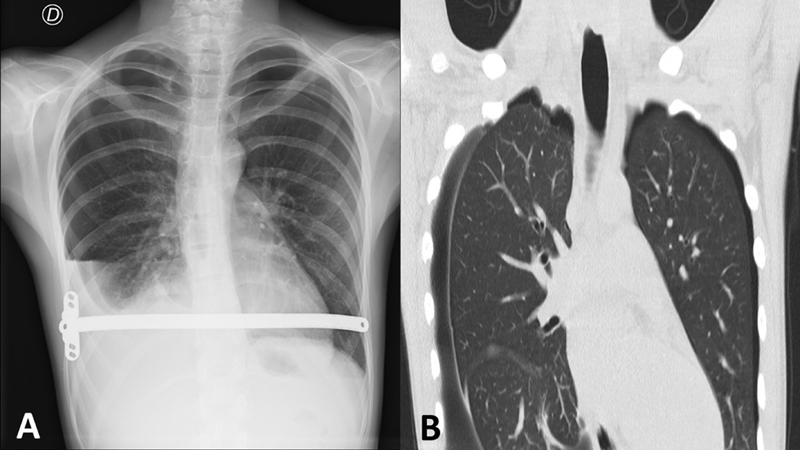

A 13-year-old male patient with marfanoid features and pectus excavatum with Haller index 4 and correction index of 38% underwent the Nuss procedure with cryoanalgesia 9 days prior, which transpired uneventfully. Preoperative spirometry was normal, and echocardiogram showed light aortic valve dilation. A month later, during a routine outpatient checkup, he referred middle abdominal pain, denying respiratory symptoms nor thoracic pain. He presented bilateral apical and right basal hypophonesis. Chest X-ray revealed bilateral pneumothorax and right pleural effusion. Consequently, the patient was admitted to the emergency room, and a chest computed tomography was ordered, reporting right apical blebs. Bilateral thoracoscopy was performed, and apexes were checked for pulmonary blebs to rule out primary pneumothorax. In the right chest, a wedge resection of a distorted area on the apex and pleuroabrasion were done. Four air leaking eschars were found when performing lung expansion under water as leaking test, corresponding to cryoanalgesia intercostal eschars, and subsequently closed by primary suture. In the left chest, there were no blebs. However, another four pleural lesions with intact pleura in the left lower lobe were also found. Postoperative course was uneventful and chest drains were removed 48 hours after surgery. He remains asymptomatic 21 months after discharge. Cryoanalgesia in pectus excavatum is spreading due to the improvement in postoperative pain control. However, some complications may occur.